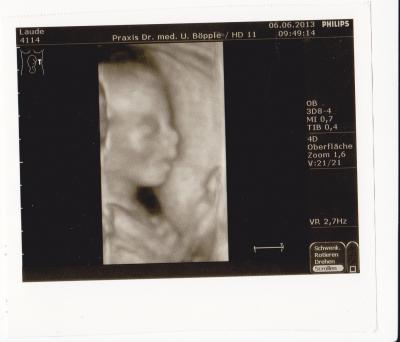

hallo ihr lieben ich hatte ja heute meinen FA termin. unserem krümel geht es super hat während der untersuchung etwas rumgezappelt... aber nicht doll.... war wohl noch nicht ganz wach leider weiß ich nicht wie groß oder wie schwer. der kopfumfang ist 5,5 cm. und der oberschenkelknochen entspricht genau 18+4 ...ist also auf den tag genau entwickelt soooo..... jetzt zum "wichtigsten" wir bekommen eine kleine prinzessin!!!! der fa meinte er könne es diesmal unterschreiben eine hand konnten wir heute ganz deutlich sehen.... und die beine..... lag mit dem gesicht nach innen und hatte die beine angezogen. kopf war oben und die beine hatte sie mir in den unterleib gedrückt ;-) sag ich doch.... eine zicke.... tritt nur dann wenn sie der meinung ist das es keiner merkt ;-) bis auf heute.... da hat sie einmal gegen den schallkopf getreten. hab auch ein schönes 3D foto bekommen. bin ich auch ganz froh drum, denn auf dem normalen schall sah sie ja doch noch etwas gruselig aus ;-) der kopf wie ein totenkopf.... und das rückrad konnte man gut sehen und die rippen...das herz, den magen......auf nem normalen foto nicht unbedingt soooo schick ;-) danke fürs daumen drücken. ich bin wirklich sehr erleichtert das es ihr gut geht. mein mann voll süß- nach dem arzt waren wir noch schnell bei rossmann und mein mann hat erstmal so ein erstlingsset in rosa gekauft er meint, jetzt kann er ja endlich shoppen gehen LG

ich habe einmalig 35 € bezahlt dafür das ich bei jeder untersuchung einen schall bekomme. eigentlich hatte ich gedacht das ich dann immer normale bilder bekomme.... aber ich habe die letzten male immer 3D bekommen!!!! meine ersten beiden 3D bilder sahen total gruselig aus.... voll das alien ;-) jetzt sieht sie ja schon richtig wie ein kleines baby aus